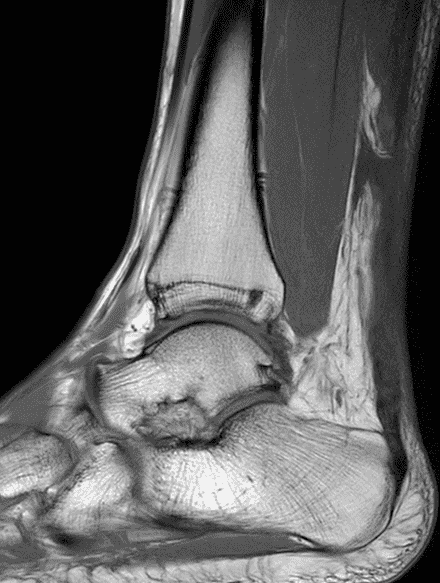

A 22 year-old male college football player presents with a “pop” and pain posterior to the right ankle during practice 1 week prior. He is unable to bear weight. Lateral radiograph (1A), sagittal fat-suppressed T2-weighted (1B), sagittal T1-weighted (1C), and transverse fat-suppressed T2-weighted images are provided. What is your diagnosis? What MRI findings affect clinical management decisions?

Figure 2: Complete Achilles tendon rupture. (2A) The lateral radiograph shows a thick and indistinct proximal Achilles tendon contour (arrows). (2B) A fat-suppressed T2-weighted image shows complete rupture of the tendon with a fluid-filled gap (yellow arrow) measuring 1.5 cm in length, located 10 cm cranial to the tendon insertion (blue arrow) and just distal to the edematous myotendinous junction (red arrow). The tear is superimposed on diffuse tendinosis. (2C) A sagittal T1-weighted image confirms the diffuse tendinosis. Fluid extends anteriorly into Kager’s fat pad (arrow) suggesting disruption of the anterior paratenon. (2D) A transverse fat-suppressed T2-weighted image through the proximal tendon shows no intact fibers (arrow), confirming the full-thickness rupture.

Acute, complete Achilles tendon rupture just distal to the myotendinous junction, superimposed on diffuse tendinosis.